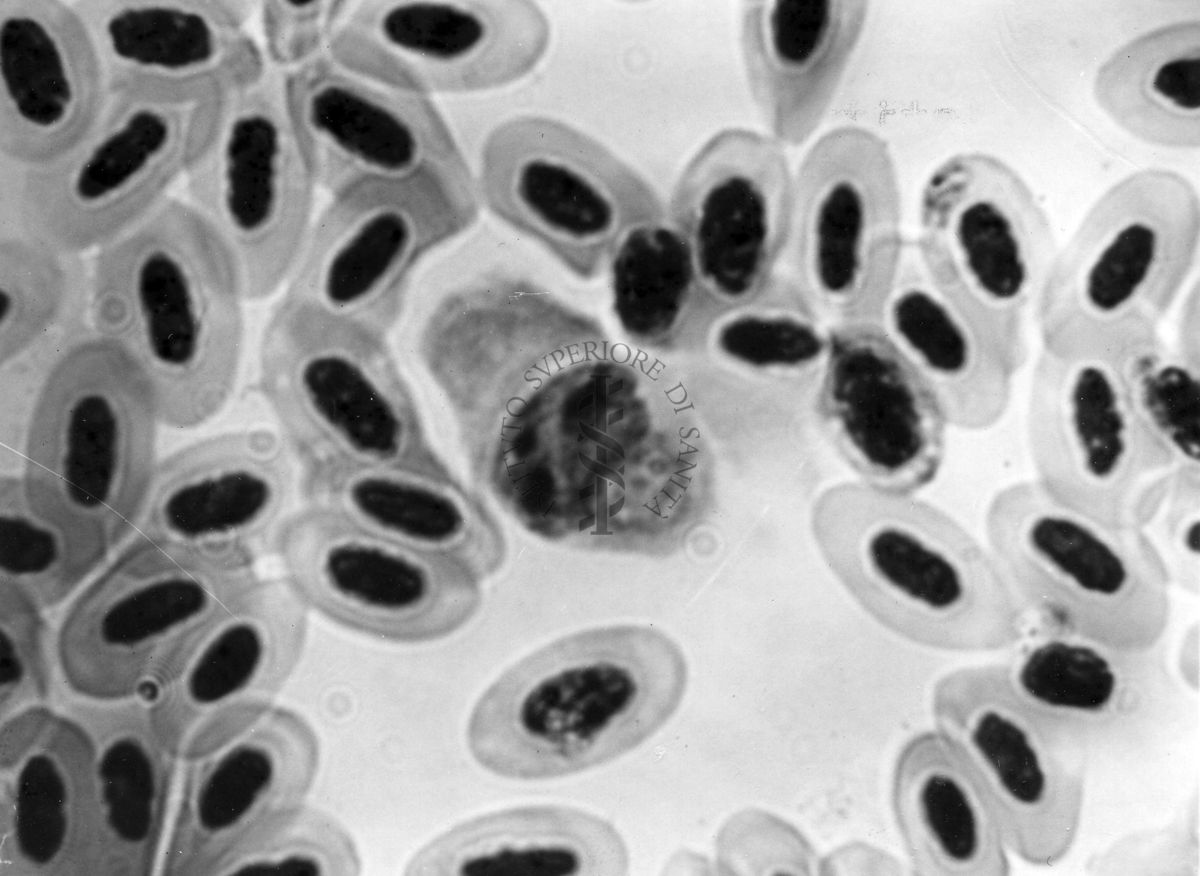

Fotografie di emoprotozoi